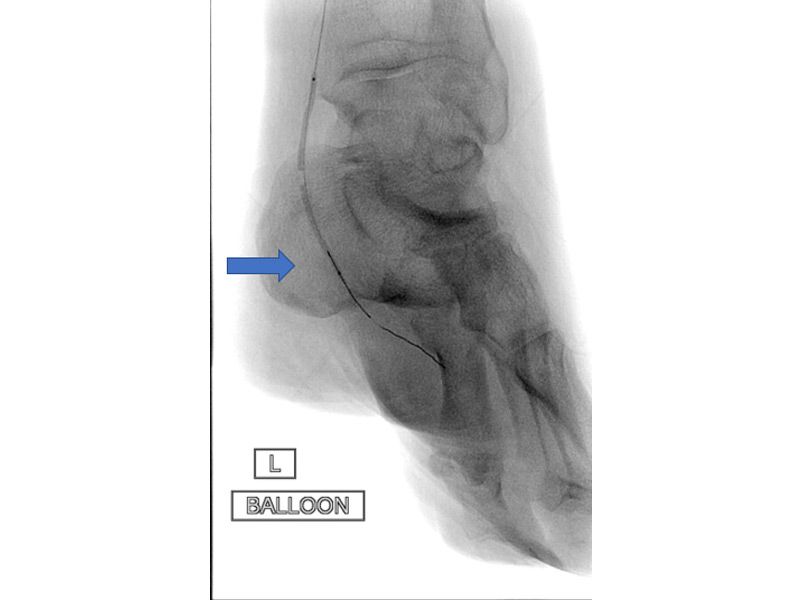

Έγινε διάνοιξη της αρτηρίας με μπαλόνι από τον συνεργαζόμενο αγγειο-επεμβατικό της ομάδας και αποκαταστάθηκε η πλήρης βατότητα του αγγείου.